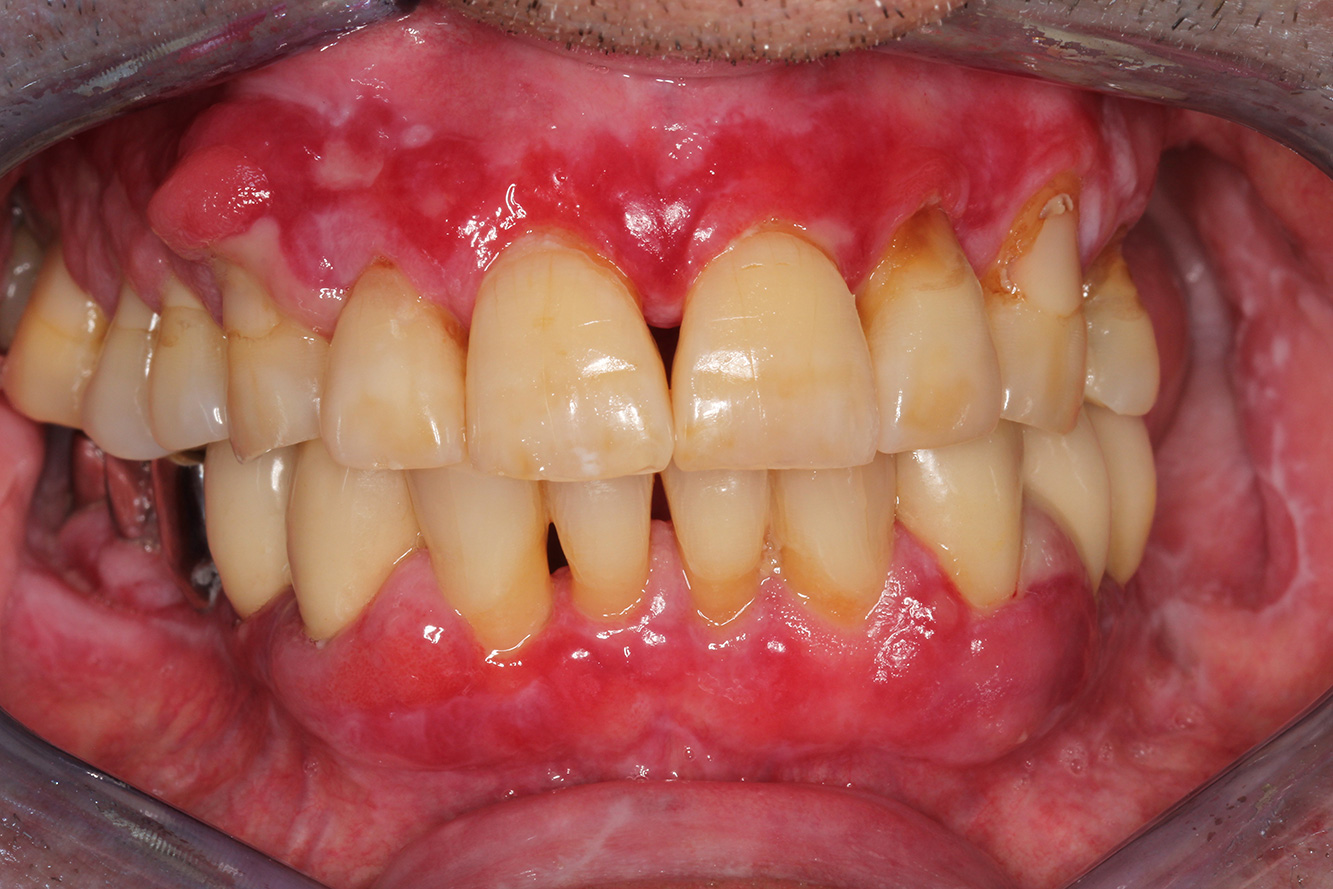

The healthy patient with pre-existing periodontal disease & peri-implantitis

A 52-year-old patient presents at a preventive care session. The patient has no systemic disease and is not taking any medication. He has had various dental treatments and also has two active carious lesions. In addition, the patient has four implants (2nd, 3rd and 4th quadrants). He is revealed to have early periodontal disease (stage IV, grade B). His periodontal condition is stable; a probing depth of Probing depths (ST) of 5 mm is only evident at the implant in region 36. Gingivitis is also identified. more

A 71-year old patient presents with having previously undergone a kidney transplant and with a history of hypertonia (high blood pressure). Due to his medical history, long-term medication with cyclosporine is required to suppress the immune system, as well as amlodipine to lower blood pressure. The patient also reports sensitive and bleeding gums. From an oral health perspective, the patient has undergone dental restoration and has eight missing teeth, pronounced gingival growth, and grade B, stage II periodontitis with active pockets and initial root caries on tooth 22. The caries risk assessment determines a moderate risk of caries (API 60). The following treatment recommendations can be determined for the prophylaxis session. more